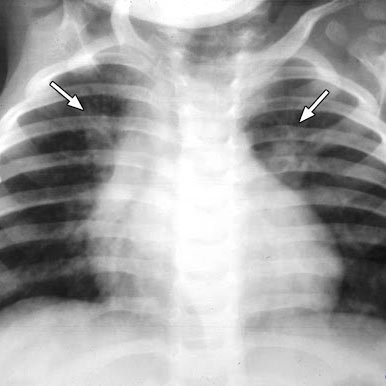

Важная роль в диагностике принадлежит результатам общего анализа крови, рентгенографии легких и бактериологического анализа мокроты.

Обзорная рентгенография позволяет выявить в легких инфильтративные двусторонние затемнения очагового, сегментарного или тотального характера. Данное исследование – основной подтверждающий критерий двусторонней пневмонии.

Для подтверждения диагноза и назначения терапии всем пациентам с подозрением на пневмонию обязательно проводят рентгенографию грудной клетки, забор мокроты с последующим ее посевом и определением чувствительности флоры к антибиотикам. Несвоевременная диагностика и позднее начало лечения сильно снижают вероятность благоприятного исхода и чреваты фатальными для пациента последствиями.

Диагностика двухсторонней пневмонии предполагает не только осмотр, аускультацию, пальпацию грудной клетки, которые могут оказаться незаменимыми на догоспитальном этапе. В обязательном порядке проводятся лабораторные исследования и рентгенография грудной клетки.

Основными исследованиями при подозрении на двухстороннюю пневмонию являются:

- Рентген, КТ грудной клетки;